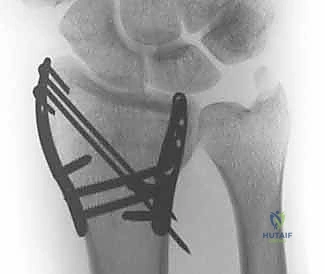

هنا تبرز عبقرية التثبيت المتناسب مع الشظايا (Fragment-Specific Fixation). يعتمد هذا النهج الذي يتقنه الأستاذ الدكتور محمد هطيف على مبدأ بسيط ولكنه معقد في تنفيذه: "لكل شظية عظمية مهمة، غرسة خاصة بها". بدلاً من محاولة إجبار العظم المفتت على التوافق مع صفيحة واحدة كبيرة، يتم استخدام مجموعة من الصفائح الصغيرة جداً (Low-profile mini-plates)، والمسامير الدقيقة، والأسلاك (K-wires) المصممة خصيصاً لتطويق وتثبيت كل عمود أو زاوية تشريحية (مثل شظية العمود الكعبري، أو الحافة الهلالية).

- استقرار ميكانيكي فائق: يوفر تثبيتاً صلباً من زوايا متعددة (Construct stability)، مما يمنع انزياح الشظايا لاحقاً.

- استعادة تشريحية مثالية: يسمح بإعادة بناء السطح المفصلي بدقة متناهية، مما يقلل من خطر التهاب المفاصل التنكسي (خشونة الرسغ).

- حركة مبكرة جداً: بفضل الاستقرار القوي، يمكن للمريض البدء في تحريك أصابعه ورسغه في غضون أيام قليلة من الجراحة، مما يمنع التيبس (Stiffness) ويحافظ على قوة الأوتار.

- غرسات منخفضة السماكة (Low-Profile): الغرسات المستخدمة صغيرة جداً ورقيقة، مما يقلل بشكل كبير من احتكاكها بالأوتار المحيطة، وبالتالي يقلل من خطر التهاب أو تمزق الأوتار بعد الجراحة.